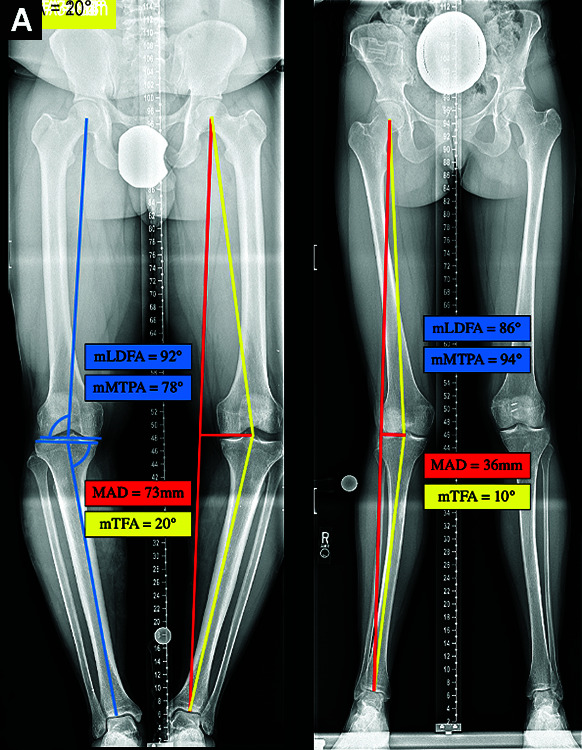

Results: The mean mechanical axis deviation (MAD) correction was 56 mm for varus deformities (n = 13) and 45 mm for valgus deformities (n = 8) with an overall mean correction of the femoral tibial angle of 15° per extremity. The accuracy of correction was 92.9% compared to the goal MAD. Two patients had peri-incisional cellulitis that resolved with antibiotics. There was no incidence of non-union, deep vein thrombosis, compartment syndrome, deep infection, or peripheral nerve palsy. Patient-reported outcome scores had clinically meaningful improvements in pain, function, and mental health.